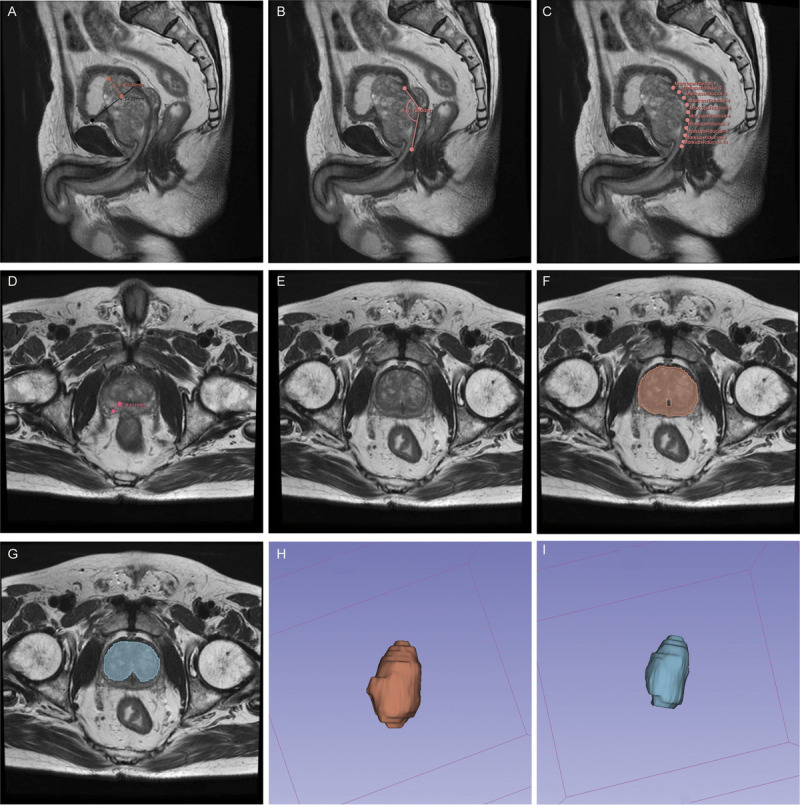

Materials and methods: A total of 137 patients with BPH who underwent B-TUEP at 2 institutions were included. Radiological features were measured in the MRIs, and the radiomics score was developed from 1702 radiomics features extracted from the prostate and transitional zone regions of interest. Three prediction models were developed and validated based on clinical-radiological features, radiomic features, and their combinations. The models were evaluated using the area under the receiver operating characteristic curve, calibration curve, and decision curve analysis.